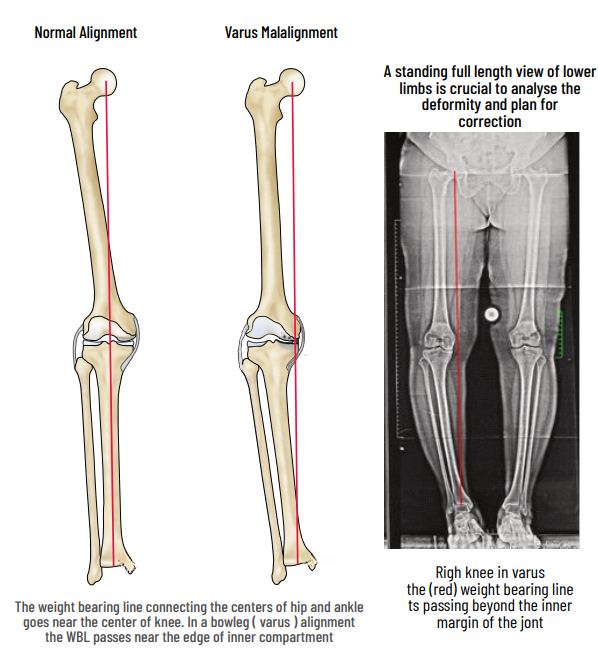

Malalignment

Faulty knee alignment (bow-leg or knock-knee) overloads one compartment, resulting in cartilage injury, meniscus tears and joint space narrowing. As the joint space reduces, the alignment also worsens leading to a vicious cycle of joint destruction and deformity. Fortunately correction of the alignment at an early stage can restore knee function and postpone joint replacement

HTO is a procedure to correct the alignment and to distribute the load to the non-involved compartment. Arthroscopy is done to assess the status of the joint and to treat meniscal tears, loose bodies & cartilage tears. Based on preoperative planning and using precision instrumentation, a partial bone cut (osteotomy) is made in the upper tibia and is slowly opened to the desired level to shift the load to the normal compartment.